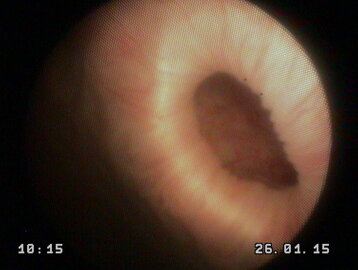

una carrellata di immagini per dare l'idea di cosa è possibile vedere con questo esame

causa di cistiti recidivanti